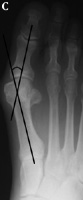

Hallux Valgus Angle

The hallux valgus angle (HAV) or hallux abductus angle is the angle formed between the longitudinal axis of the first proximal phalanx and the longitudinal axis of the first metatarsus.

Hallux VarusA.  In hallux varus or adductus the HAV is less then 5º. Normal Hallux Valgus Angle B. In normal subjects  HAV is 5º to 15º . Hallux abducto valgus is mild when HAV is 16º to 25º,Moderate Hallux Valgus C. moderate  when HAV is 26º to 35º, and severe Severe Hallux Valgus(D) when HAV is greater than 35º.